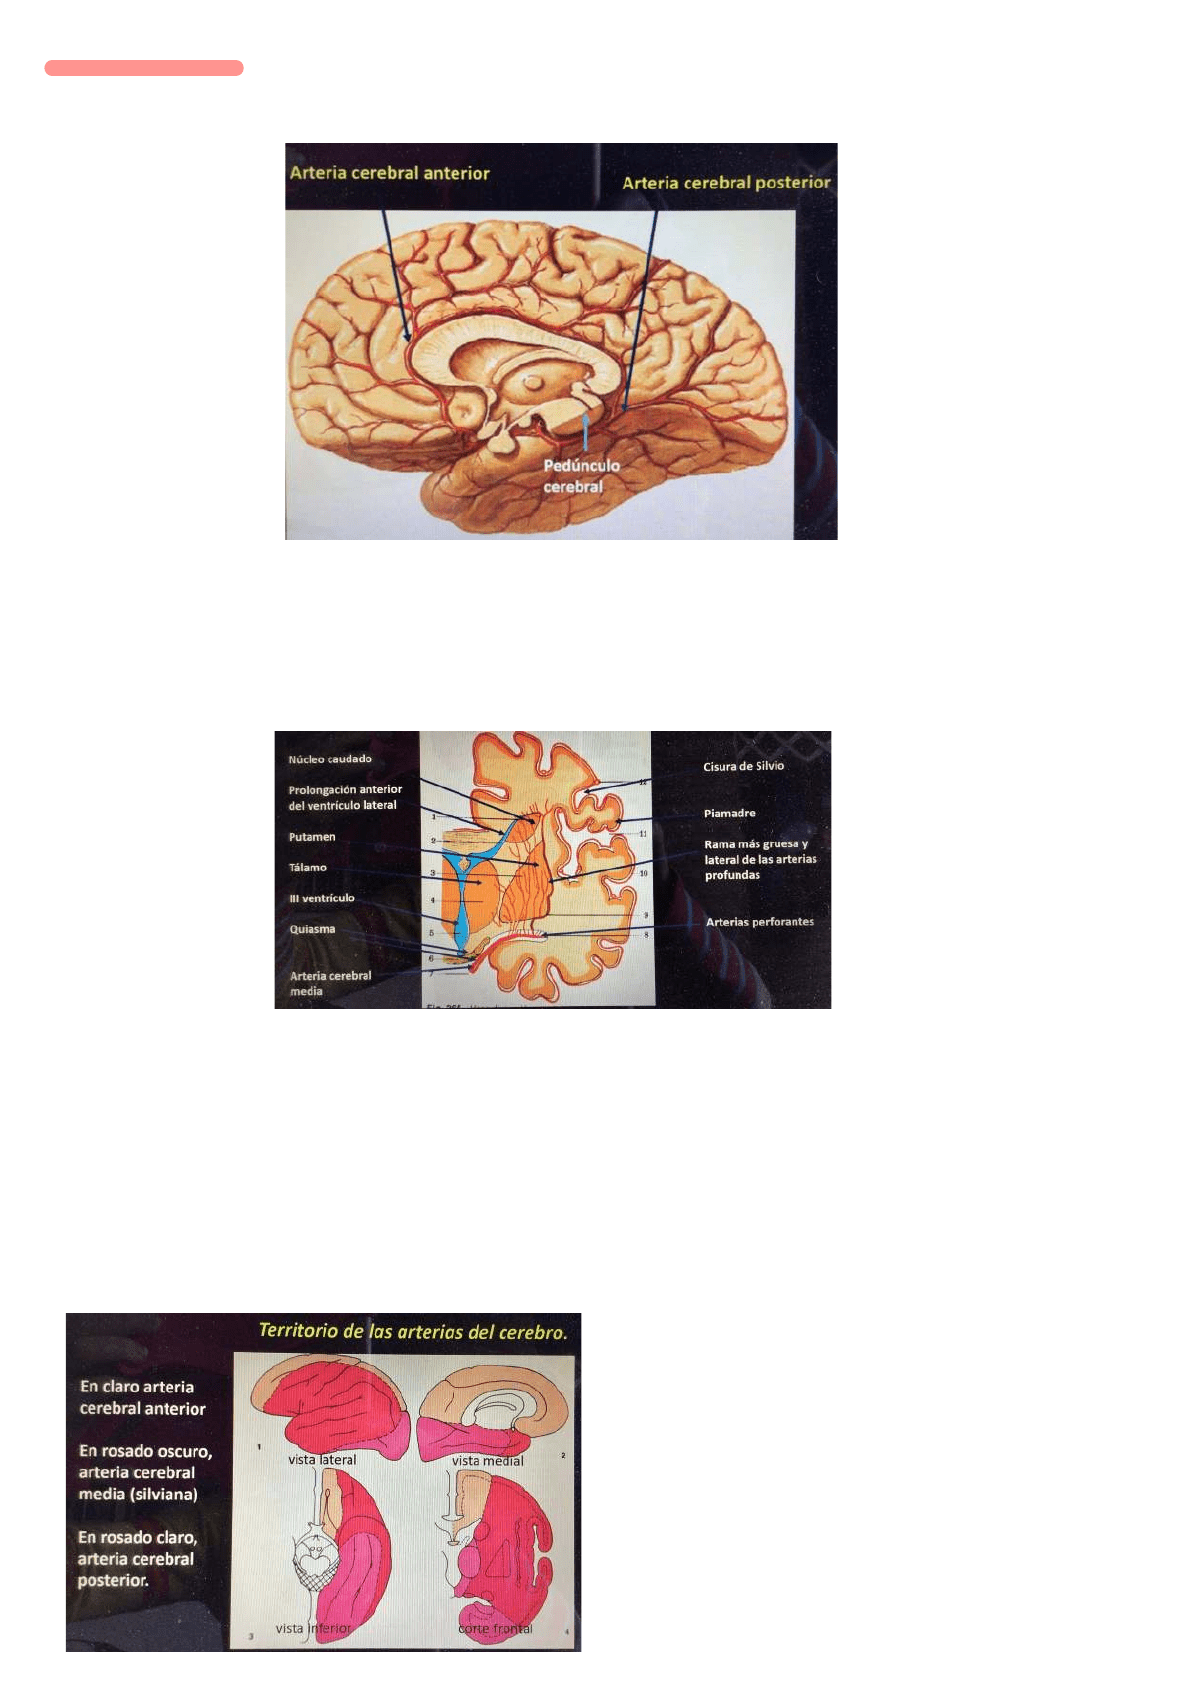

La primera es la cerebral anterior: que se dirige hacia adelante

Cerebral media/silviana: que se dirige a la cisura de Silvio

Comunicante posterior: se dirige a la base del cerebro y forma uno de los lados del polígono de Willis

Arterias superficiales

Arterias cerebrales anterior: se genera en la carótida interna, comienza hacia adelante y hacia la cisura longitudinal del cerebro pasando por encima del

nervio óptico. Se aplica a la rodilla del cuerpo calloso y se dirige hacia atrás para terminar como arteria pericallosa.

Da irrigación a la corteza cerebral y el cuerpo calloso. Cara interna del lóbulo frontal y las circunvoluciones frontales ascendentes.

Arteria cerebral media: nace directamente de la carótida interna NO participa en el polígono, penetra en la cisura de Silvio

Arteria cerebral posterior: nace de la terminación del tronco basilar a nivel del espacio interpeduncular. Se va hacia atrás pasando por la cara lateral del

pedúnculo cerebral al que contornea y sigue el borde medial del hemisferio y termina en la cara medial en el lóbulo occipital.